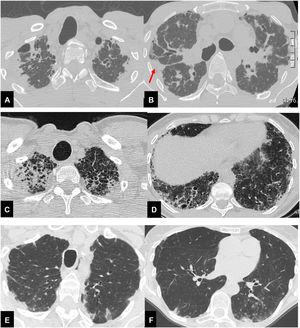

Radiological analysis, performed in consensus by a chest radiologist (SP) and a pulmonologist expert on imaging (LSF), consisted of the visual scoring of each CT finding.7 Furthermore, patients were subclassified into three groups: CT evidence of standalone PPFE (group I); PPFE plus CT evidence of a coexisting ILD (group II); PPFE plus signs of airway disease (group III) (Fig. 1). Clinical data collected and visual CT analysis are reported in the supplemental materials.

Thirty-seven year-old male (A,B), with surgical biopsy-proven PPFE and severe impairment of PFT (FVC 27% FEV1 25% DLCO 31%). CT scan shows bilateral, dense pleural and subpleural fibrosis suggestive of PPFE, in the upper and mid lung regions. The elastotic tissue is also present in the fissures, with particular evidence for the right one (red arrow). Scattered traction bronchiectasis are present in the surrounding dense elastotic fibrosis.

Sixty-seven year-old female (C,D), with diagnosis of familial pulmonary fibrosis. Surgical lung biopsy documented: PPFE + UIP pattern. CT scan shows brobable UIP pattern in both lower lobes, mainly on the right associated with pulmonary ossifications e traction bronchiectasis.

Seventy-eight-year-old female (E,F), affected by Sjogren disease, with diagnosis of bronchiolitis Nocardia abscessus related. PPFE is present in both upper lobes associated with centrilobular nodules and mucus plugging in the bronchi in the left lower lobe.